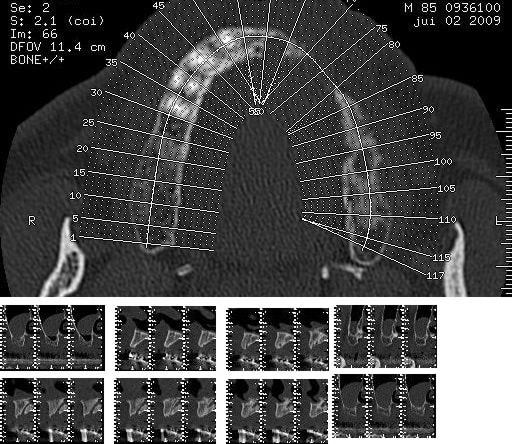

en haut j'ai déposé un bridge de 4 dents,(17/16/15/14) et j'ai fait une "augmentation" du sinus par la racine mesiale de 16, (avec un balloon)un comblement de sinus par fenetre latérale n'etant pas envisageable pour le moment.

interet: pas de suite, ni douleur ni autres.

inconvenients: expansion limité, pas de controle direct

J’en reviens au fait que j'ai mis sur nonol un cas de sinus fait au balloon, c'est ce qui me paraissait important, et que la discussion s'étale sur la planification du travail.

Mais il me semblait important de dire que le système balloon était très praticien dépendant et ne m'a pas semblé être un progrès ni une simplification par rapport aux méthodes que j'utilise d'habitude.

et le balloon j'etais enthousiaste, mais j'ai peté deux balloon pour le sinus droit et ça m'a un peu gonflé (pas le ballon) j'ai donc fini en manuel (pas Chanavaz) et resultat bof.

je connais le produit d'angio mais ne sais pas le nom je vais chercher ce serais plus pratique

d'accord pour le sexe (what else?) et pour le ballon il m'en reste un donc je vais refaire un essai, mais je vais adapter "ma" méthode je vous dirais (en principe mercredi 15)

mais le kit est trop complexe pour le moment donc je vais essayer autre chose.